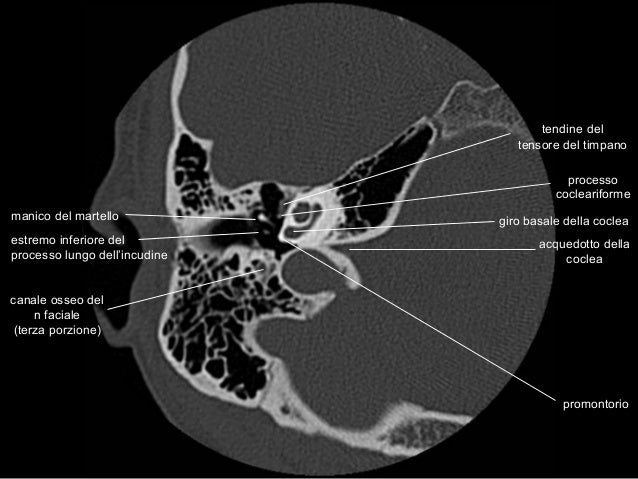

Anatomia Rocca TC - CT Temporal Bone Anatomy

Anatomia Rocca TC - CT temporal bone anatomy www.slideshare.net

anatomia temporal coclea timpano acquedotto